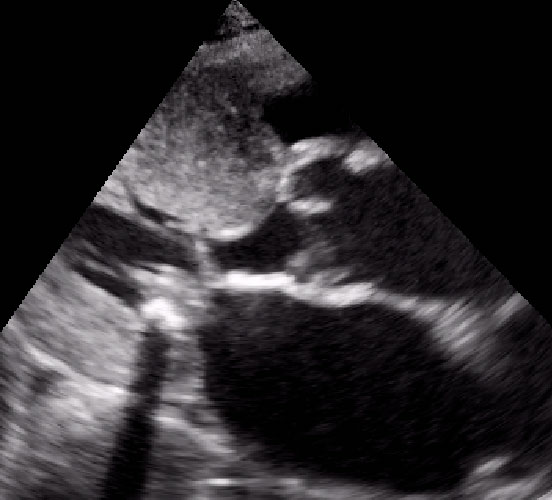

Cardiomiopatia ipertrofica ostruttiva

Laura Massironi